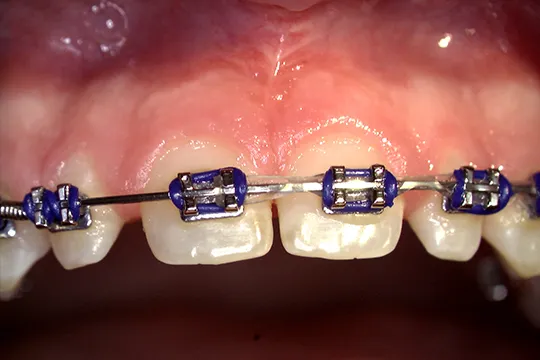

Frenectomy

Before